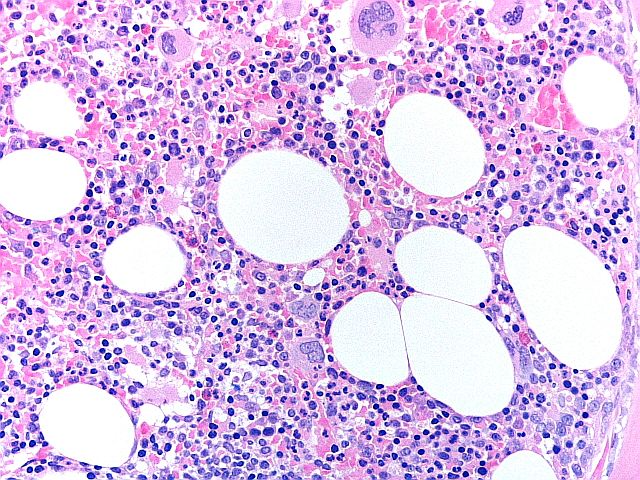

H&E - Program przeszczepu szpiku kostnego

To doskonały preparat z biopsji przeszczepu szpiku kostnego, ze zrównoważonym barwieniem H&E, dobrą szczegółowością chromatyny i selektywnym barwieniem poszczególnych typów komórek w szpiku kostnym. Preparat uzyskał ocenę 9/10.